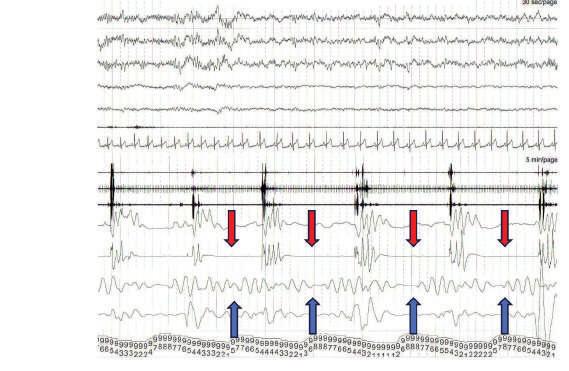

A polissonografia é um exame realizado à noite, em que são monitorados vários parâmetros simultaneamente, conforme demonstrado na Figura 1.3. Normalmente, esse exame é solicitado quando temos uma suspeita de algum distúrbio do sono, como síndrome da apneia obstrutiva do sono (SAOS), por exemplo. A polissonografia pode ser realizada numa clínica ou na própria casa do paciente, dependendo da suspeita clínica.1,4

Figura 1.3. Montagem de polissonografia.

Fonte: elaboração do autor.